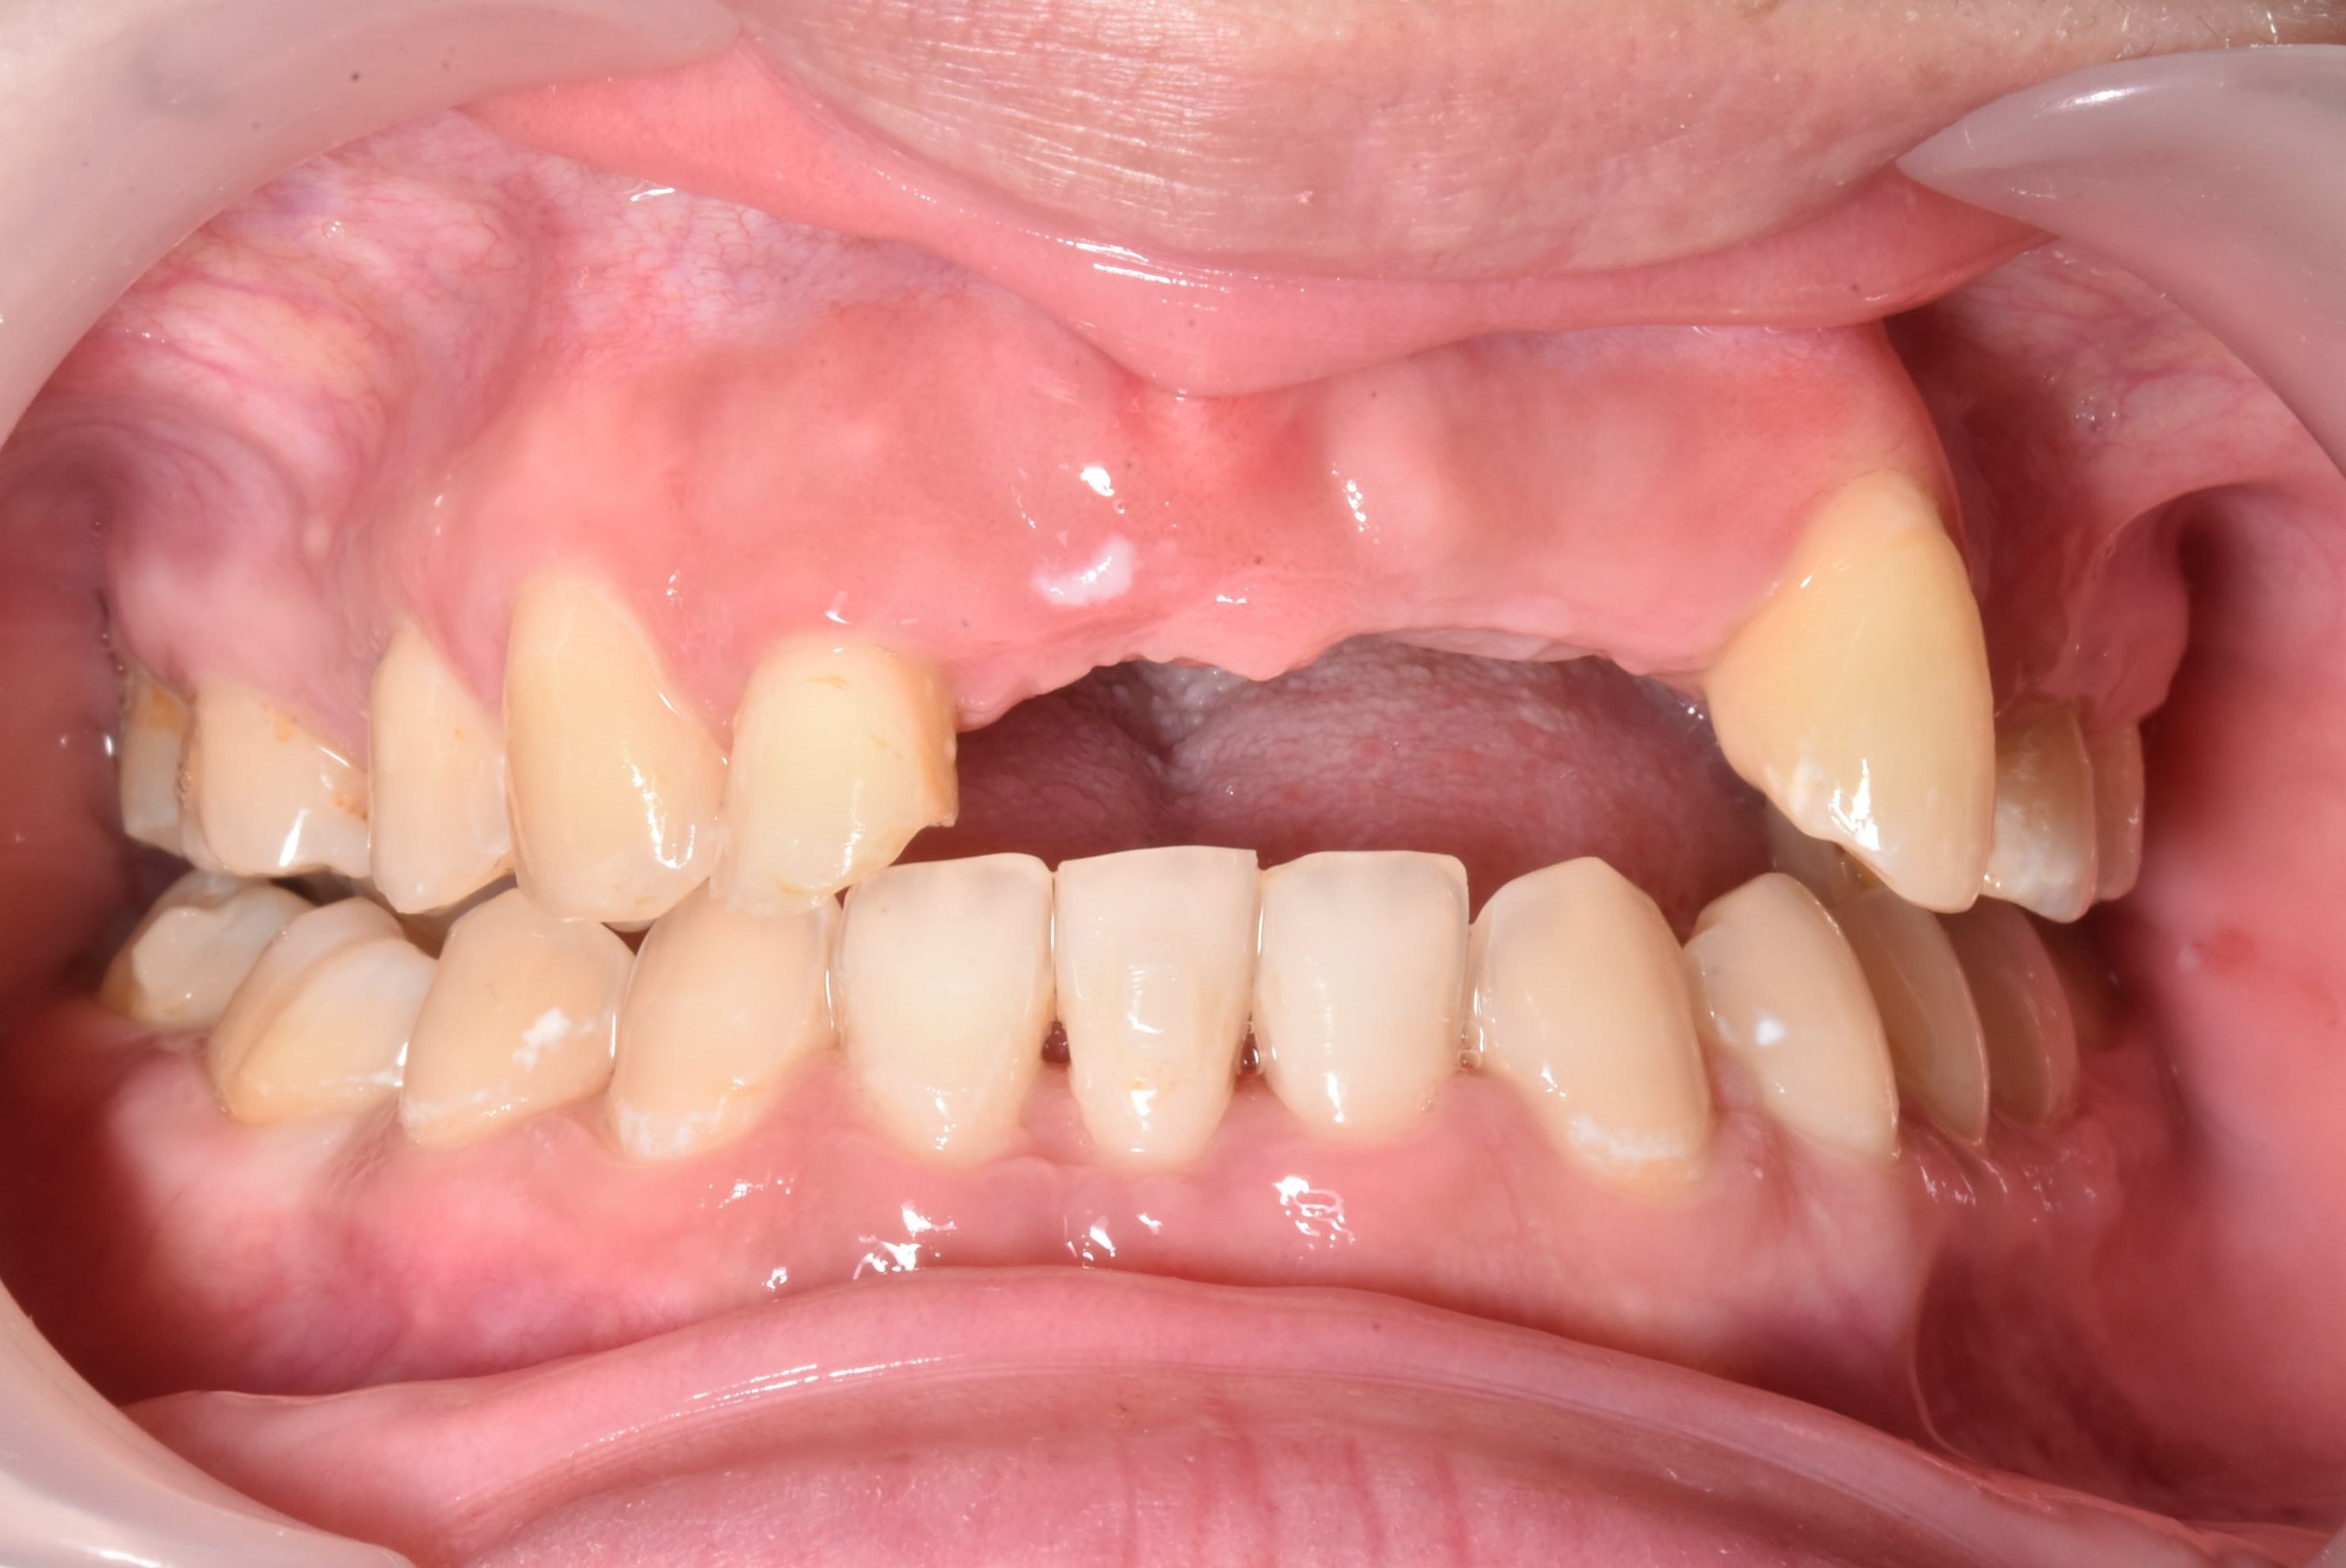

案例二

骨頭明顯凹陷